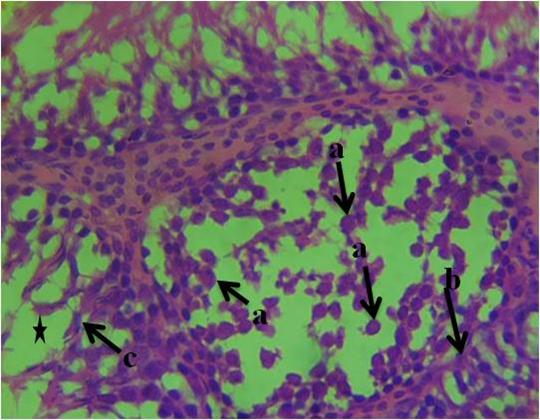

The histological section of group 1 (control) animals given water and feed alone as represented in figure 1 shows normal spermatogonia, primary spermatocytes, interstitial cell of Leydig, connective tissue, spermatids and seminiferous tubules with the presence of densely packed spermatozoa. In figure 2, the histological section revealed proliferation of atypical germ cells within the seminiferous tubules, degenerated connective tissue, necrotic spermatids and few/absence of spermatozoa within the seminiferous tubules. Figure 3 revealed necrotic spermatids, degenerated connective tissue, Leydig cell necrosis, necrosis of spermatogenic cells and deformed seminiferous tubule with very scanty spermatozoa.

Figure 2: Photomicrograph of testis of group 2 animals given 20ml/kg of Garri effluent showing, a-proliferation of atypical germ cells within the seminiferous tubules, b-degenerated connective tissue, c-necrotic spermatids and few/absence of spermatozoa within the seminiferous tubules (star). (H&E). 400x magnification.